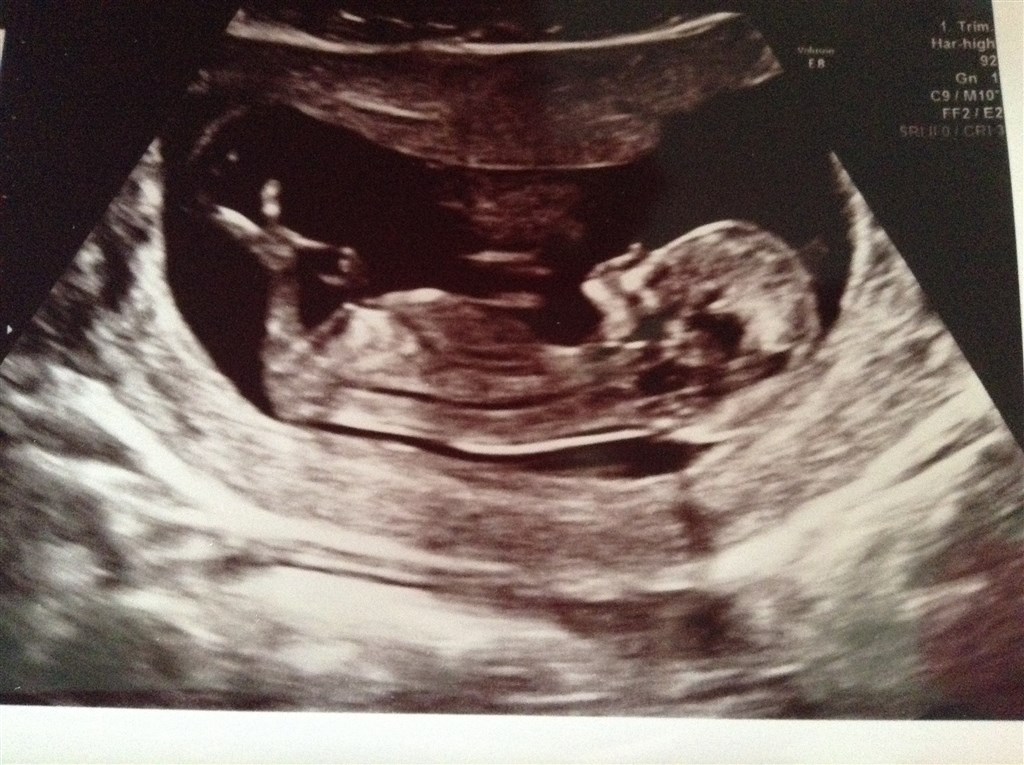

Så var vi til nf idag, og alt så bare super fint ud

hun skød det til at blive en pige

blev rykket fra 1/7 til 4/7

Nøøøøj vi glæder os! Og risikoen lød på 1:20.000 så det er perfekt